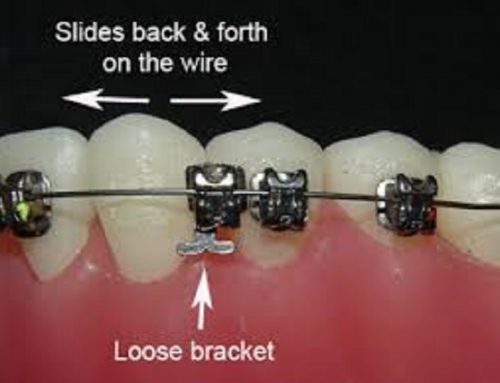

Modules are the small rubber or elastic rings that help keep the archwire attached to each bracket. They come in different colors and are replaced at every orthodontic appointment.

Wires are the metal parts that do the heavy work of moving your teeth into alignment.

Even if it seems minor, a missing module or a wire sticking out can affect the movement of your teeth and cause discomfort. This is why contacting your orthodontist in Hurghada is so important.

A loose wire can shift, bend, or break – affecting the alignment process